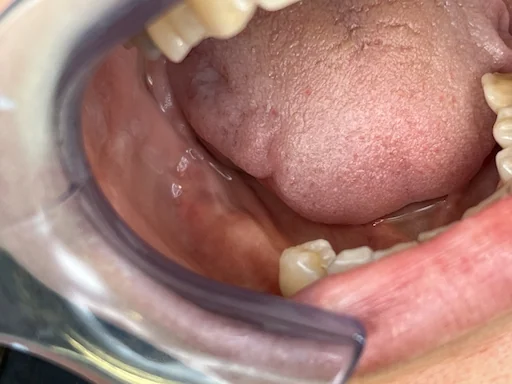

Patientenfall Implantologie - Zähne 45, 46, 47 - Fehlende Zähne in Frontansicht

Schritt 1

Der Patient stellt sich mit fehlenden Zähnen 45, 46 und 47 bei uns vor. Die Voruntersuchung zeigt, dass der Abstand zum zentralen Nervenkanal, der Lippe und Wange versorgt, sehr gering ist.

Dadurch ist es nicht möglich, ein Standardimplantat zu setzen, das zwischen 9 und 11 mm benötigt.